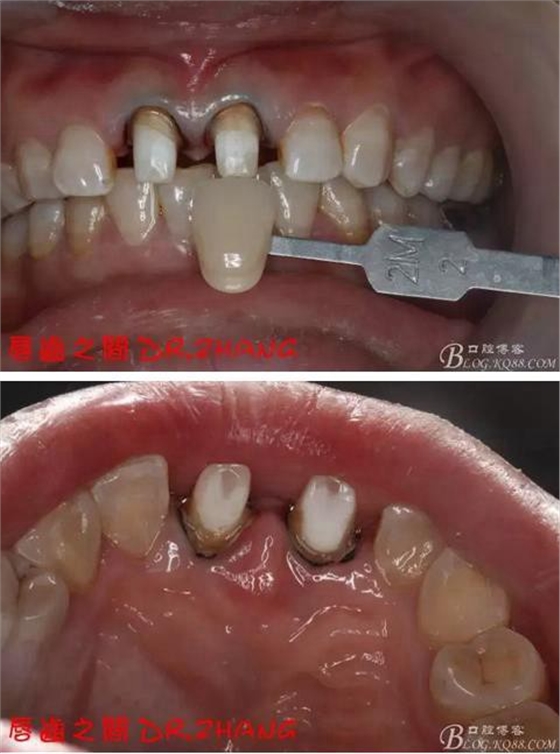

檢查:11 21金屬烤瓷冠 21根尖部牙齦紅腫 牙痛 叩(+++)冷刺激無(wú)反應(yīng) 11無(wú)不適癥狀 全口牙周情況良好

復(fù)診:腫脹明顯消失 患者自訴感覺(jué)良好 溝通后決定拆除11 21兩顆烤瓷冠后重新修復(fù) 去冠器直接去冠 去除11根管內(nèi)的充填物 15#K銼疏通根管 11 21根長(zhǎng)均為16MM平斷面 薩尼S3系統(tǒng)機(jī)擴(kuò)至2S 期間不斷用氯己定和鹽水交替沖洗 吸潮紙尖干燥根管后06 25#試尖

牙體預(yù)備后 硅橡膠取模 臨時(shí)牙恢復(fù)形態(tài)

總結(jié):沒(méi)有術(shù)前照片 預(yù)備牙體過(guò)長(zhǎng) 顏色還是有差距